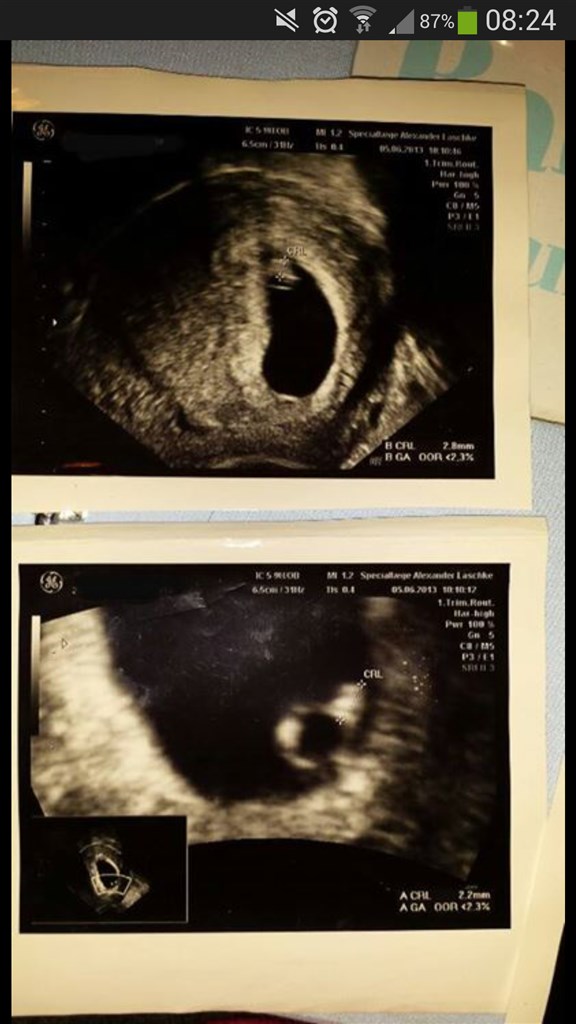

Vi har idag været til TS, og hold da op en morgen! Lægen starter med at finde en lille fis som måler 13 mm og et fint bankene hjerte. Den målte lige efter bogen, så det passer med at jeg er 7+4 idag. Det var SÅ vildt

Så kigger han lidt videre, og hov.... Så fandt han sørme en blommesæk mere! Og et lille hjerte der banker.. Men tvillingen er dog meget mindre end den første og målte kun 5 mm.

Billedet viser det foster som målte 13 mm. Og sjovt nok ligner det et lille menneske med arme og ben... Jeg fik desværre ikke et billede af det andet foster, det beholder klinikken til næste scanning.